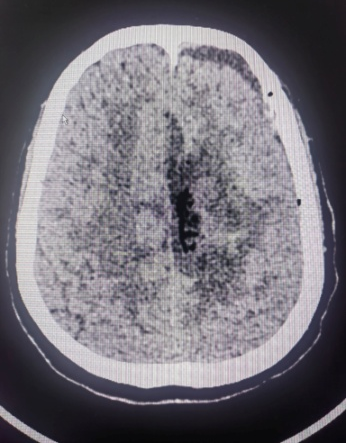

患者系中年女性,因出现偏侧肢体活动不灵和头痛症状,经检查发现颅内大脑镰旁长有一直径7cm的巨大肿瘤。肿瘤位于大脑的运动功能区,血供丰富,这一区域的手术风险极大。在决定手术治疗之前,神经外科医生与患者家属进行了充分的沟通,详细解释了手术的必要性、可能的风险和并发症,包括出血、感染、血管和神经损伤以及脑功能障碍等。家属在充分了解情况后,同意进行手术。面对这一复杂病例,我院迅速组织了由神经外科、麻醉科、心内科、输血科等多个科室的专家团队进行会诊,共同制定了先介入栓塞,再手术切除的治疗方案。

神经外科血管介入组曲友直副教授、崔刚副教授和高攀主治医师对肿瘤进行了瘤栓塞治疗,有效减少了肿瘤的血供,为后续的手术切除降低了风险。栓塞治疗后,神经外科王睿智副主任、高李贵副教授和董全主治医师在麻醉科、心内科、输血科等科室的全力配合下,凭借精湛的医术和丰富的临床经验,成功为患者切除了病变。手术过程中,麻醉科吕建瑞主任团队全程监控患者的生命体征,确保麻醉安全;心内科团队随时准备应对可能出现的心脏问题;输血科团队则确保充足的血液供应,以备不时之需。多学科的通力合作,为手术的成功提供了坚实的保障。

术后,患者被送至NICU进行密切观察,神经外科护理团队提供了精心的护理服务。在医护人员的共同努力下,患者恢复平稳,未出现任何并发症,并于近日顺利出院。